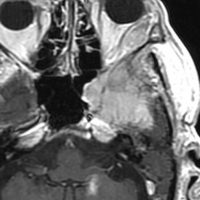

左は,造影剤を使ったガドリニウム増強MRIです。腫瘍が白く丸く見えます。右はフレア画像で,腫瘍の周囲の脳浮腫(脳のはれ)です。左前頭葉が,かなり強くはれています。この腫瘍は小さいのですが,脳のはれが強すぎるので手術摘出したほうがいいです。浮腫が悪化すると,てんかん発作や認知機能低下がでる可能性があります。